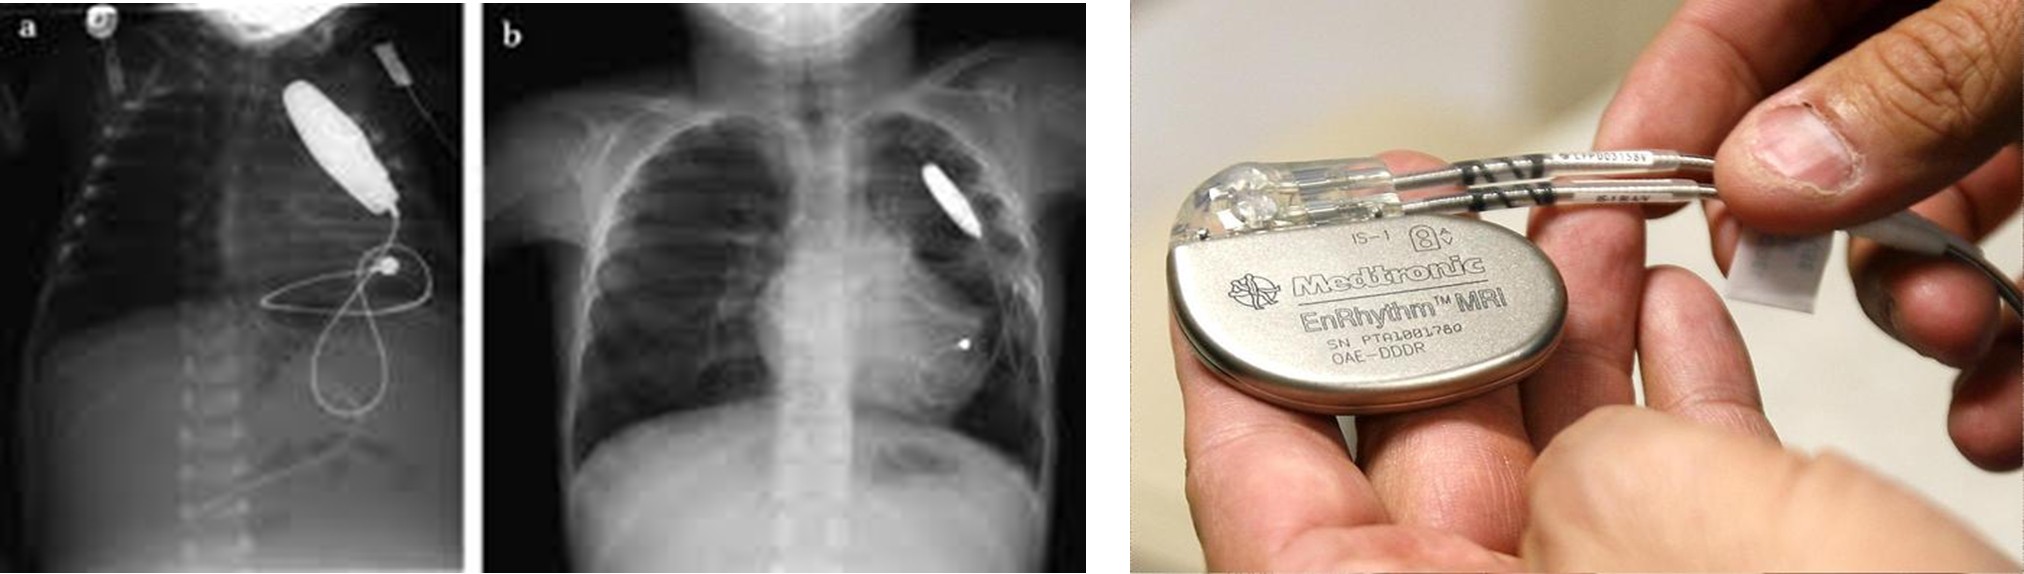

Pacemaker implantation if chronotropic incompetent and refractory to medications.

Pacemaker/ICD: In cases of high-grade AV block or high-risk ventricular arrhythmias.

- A six-year-old girl gets a Permanent Pacemaker implanted!